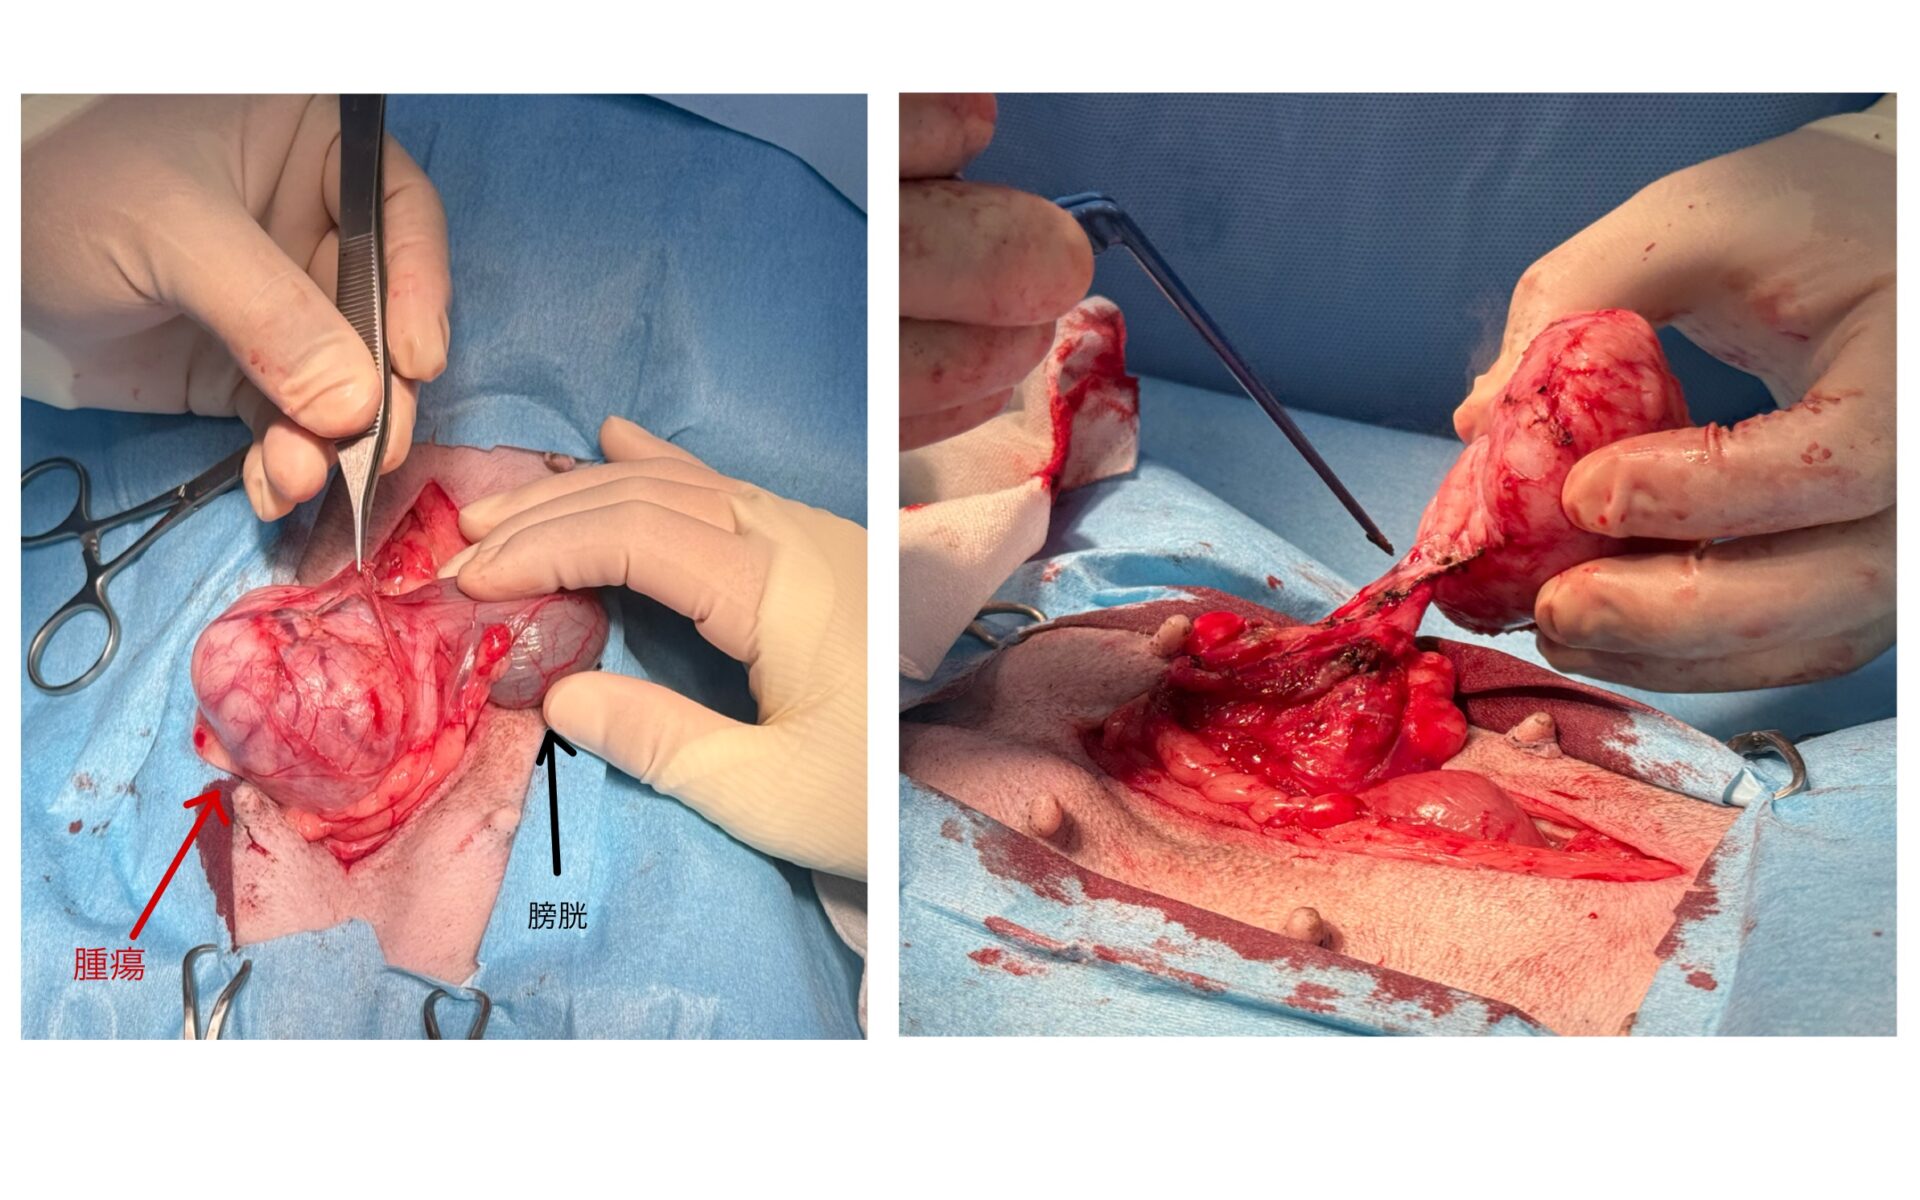

下腹部の腫れは肉眼で確認できるほどの大きさでした。

卵巣子宮の摘出後、膀胱を反転させ膣腫瘤にアプローチしました。膣腫瘤は境界明瞭であり膣筋層からの剥離も容易でした。摘出後切開した膣を縫合し、常法に従い閉腹しました。

術後の病理組織検査では、平滑筋腫であり完全切除と診断されました。術後も良好に経過しております。